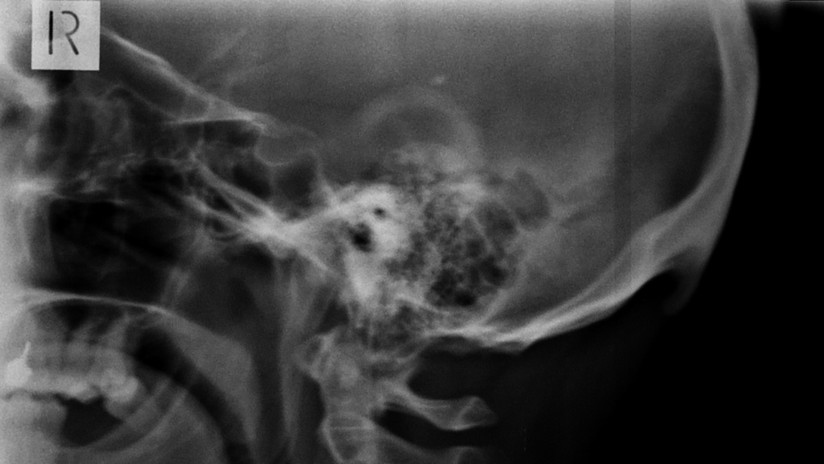

Esa actividad, dolores y rigidez de cuello aparte, está provocando un cambio en la forma del cráneo humano, afirman investigadores australianos. El cambio se viene observando desde hace algún tiempo y se trata de un hueso en forma de pico, llamado protuberancia occipital externa, que aparece en la parte posterior de la cabeza, un poco por encima el cuello. Este puede sentirse al tacto y a veces incluso puede resultar visible en personas calvas.

Tras estas observaciones, el científico decidió llevar a cabo unas investigaciones para determinar el alcance de la propagación de la anomalía. En 2016, lideró un estudio que analizó a 218 personas de entre 18 y 30 años de edad. El trabajo, publicado en la revista Journal of Anatomy, mostró que el 41 % de los participantes tenían en su cabeza ‘picos’ de más de 10 milímetros, mientras que en un 10 % de los examinados superaban los 20 milímetros.

En otra investigación, publicada en febrero de 2018 en la revista Nature, Shahar se centró en determinar la edad de las personas que contaban con ese tipo de formaciones. En el estudio participaron 1.200 individuos de entre 18 y 86 años, y el análisis concluyó que era “significativamente más probable” encontrar estas protuberancias entre los participantes de entre 18 y 30 años. Morfológicamente hablando, las nuevas generaciones están adquiriendo una característica corporal anómala.